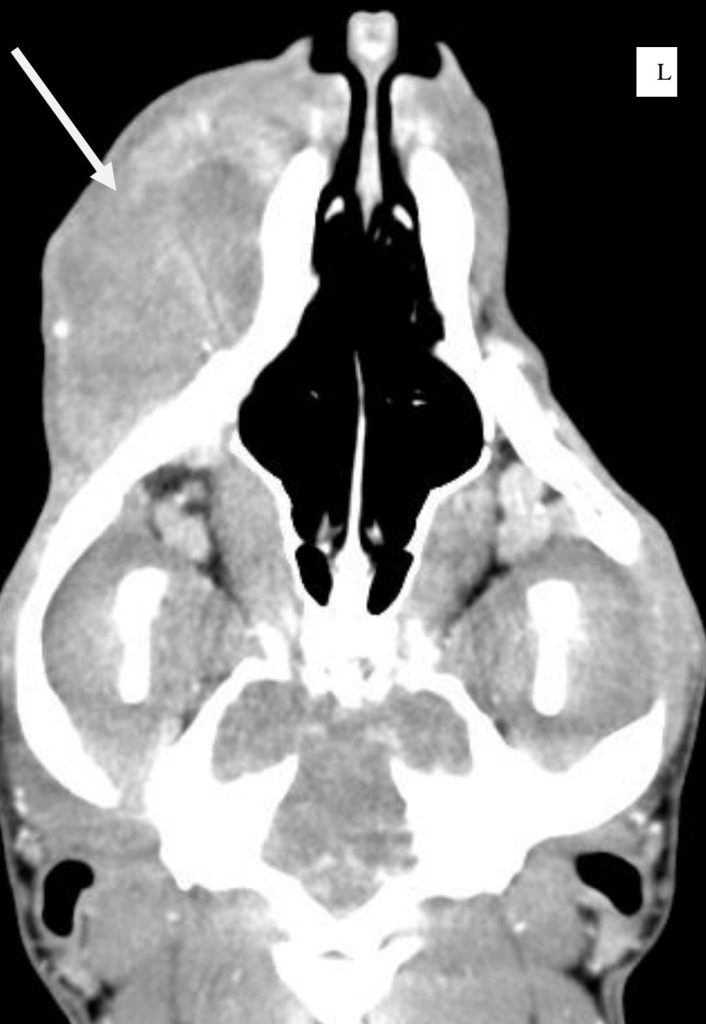

Fibrosarcoma CT felvétele kutya állcsontjánál